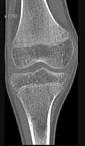

问题 男,46岁,膝关节疼痛,结合图像,最可能的诊断是()

选项 A.骨质硬化 B.骨质疏松 C.骨质软化 D.骨髓瘤 E.转移瘤

答案 B